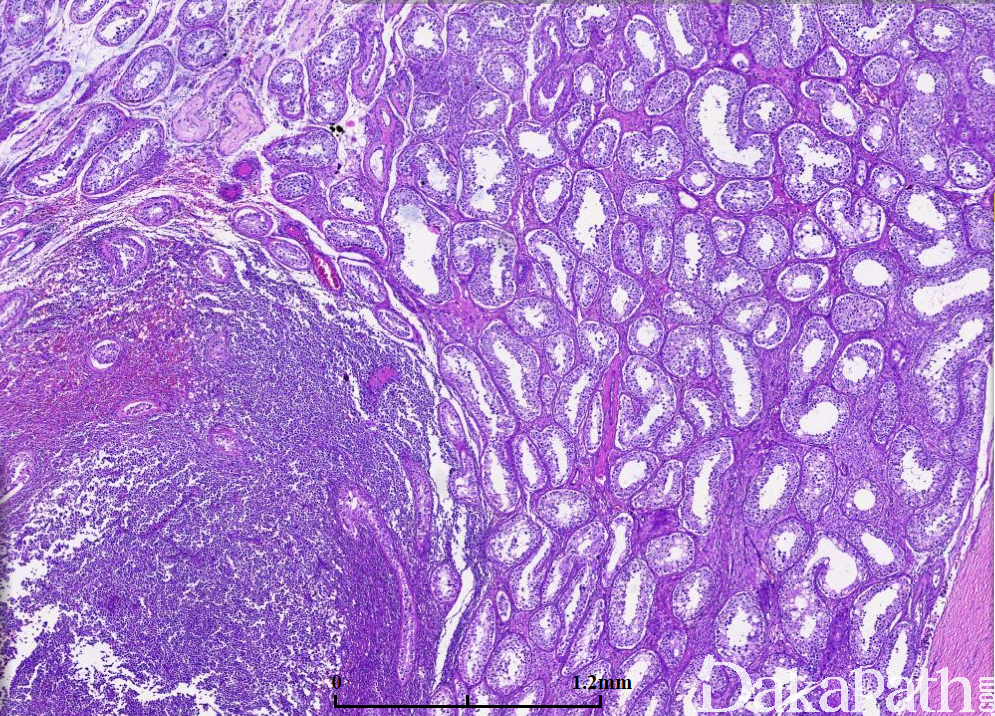

镜下肿瘤中央区域曲细精管消失,周边区表现为曲细精管间浸润,并浸润曲细精管;

肿瘤由大的淋巴细胞构成,圆形或卵圆形,核形不规则,偶尔可见分叶核,核仁清楚,胞质稀少;

周围生精小管内无小管内原位生殖细胞肿瘤。